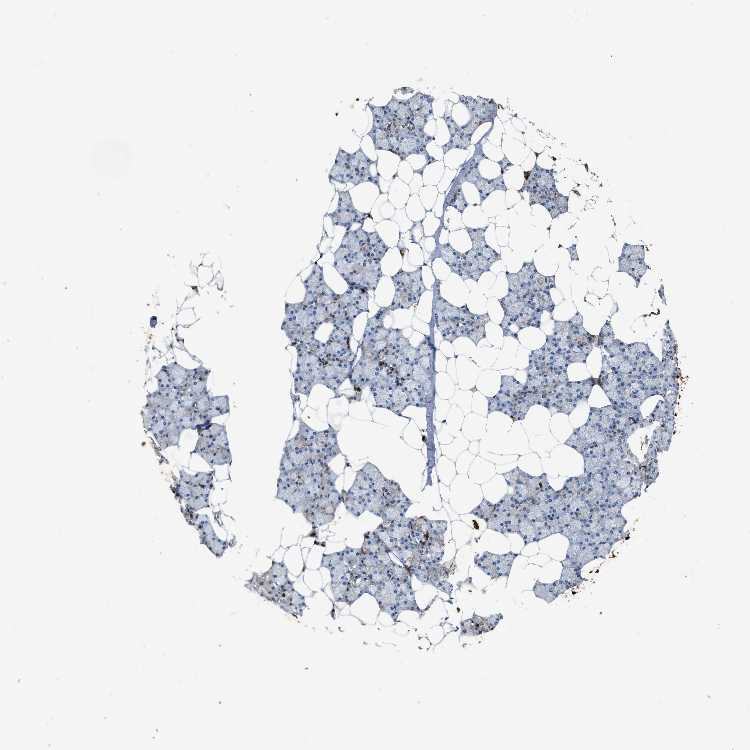

SALIVARY GLAND - Antibody stainingi

Antibody staining in the annotated cell types in the current human tissue is reported as not detected, low, medium, or high, based on conventional immunohistochemistry profiling in selected tissues. This score is based on the combination of the staining intensity and fraction of stained cells.

Each image is clickable and will lead to virtual microscopy that enables deeper exploration of all samples and also displays staining intensity scores, fraction scores and subcellular localization as well as patient and tissue information for each sample.

Antibody HPA051235Antibody CAB018584

Glandular cells LowLow